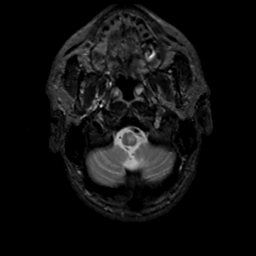

MR Study #13, May 19, 1991 -- Slice #4

[Home][Help][Clinical][Tour 1][Tour 2] Slice 4